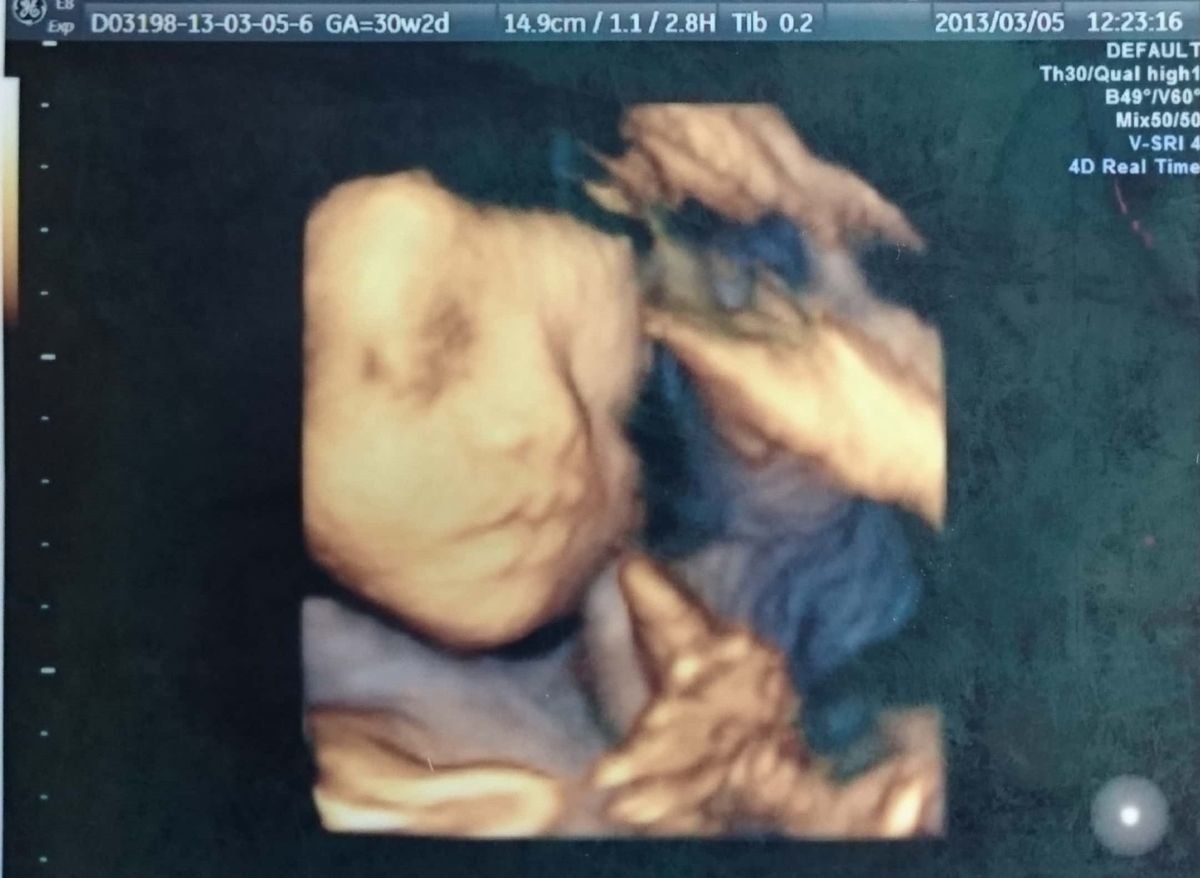

妊娠30週のエコー写真 再びの3D写真。今見ると、すでに面影あり

14.9cm(3Dのエコー写真では何を測ったかの情報記載がないため、「9.6cm」という数字が何を表しているのかは不明。)

見たいと言ったら見せてくれた3Dエコー。表情がしっかりと分かります。その当時は、「赤ちゃんの人形みたいに見えて、そんなに特徴が分からないな」と思いましたが、今見てみると、息子の寝顔そのまま。面影がかなりあります。私のおなかも大きくなり、歩くペースも遅くなっていた頃でしたが、先生に確認をして隣県へ2泊3日のマタニティ旅行をしました。